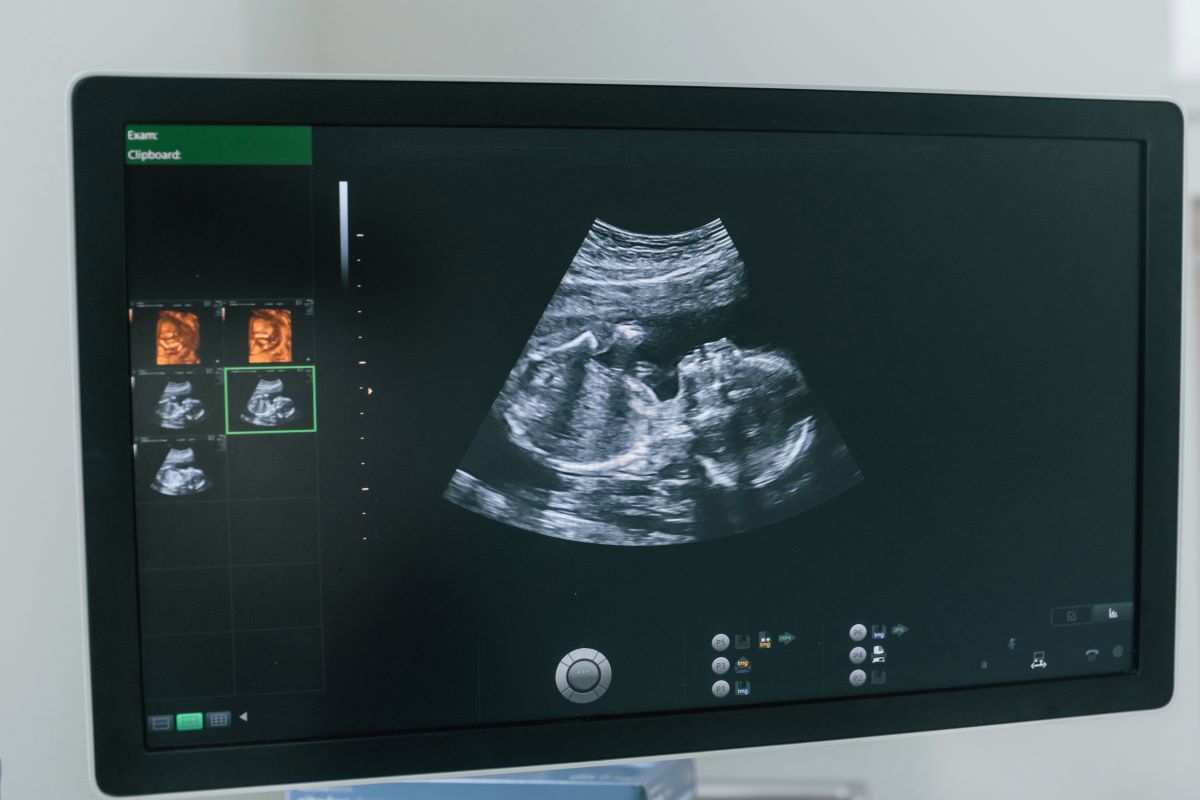

L'échographie 3D représente une avancée technologique majeure dans le suivi de grossesse. Cette technique permet d'obtenir des images en trois dimensions du fœtus, offrant une visualisation beaucoup plus détaillée que l'échographie 2D traditionnelle. Contrairement aux idées reçues, la détermination du sexe ne dépend pas tant du type d'échographie (2D ou 3D) que de plusieurs facteurs essentiels.

La fiabilité de la détermination du sexe dépend principalement de trois éléments : le nombre de semaines de grossesse, la qualité de l'appareil utilisé et la position du bébé. À 27 semaines de grossesse, les organes génitaux sont normalement bien formés et clairement visibles, ce qui rend l'identification du sexe particulièrement fiable à ce stade avancé.

Les professionnels de santé utilisent des critères précis pour identifier le sexe du bébé. Pour un garçon, ils recherchent la présence du pénis et du scrotum, tandis que pour une fille, ils observent les lèvres génitales. À partir de 16 semaines d'aménorrhée, ces structures sont généralement suffisamment développées pour permettre une identification fiable.